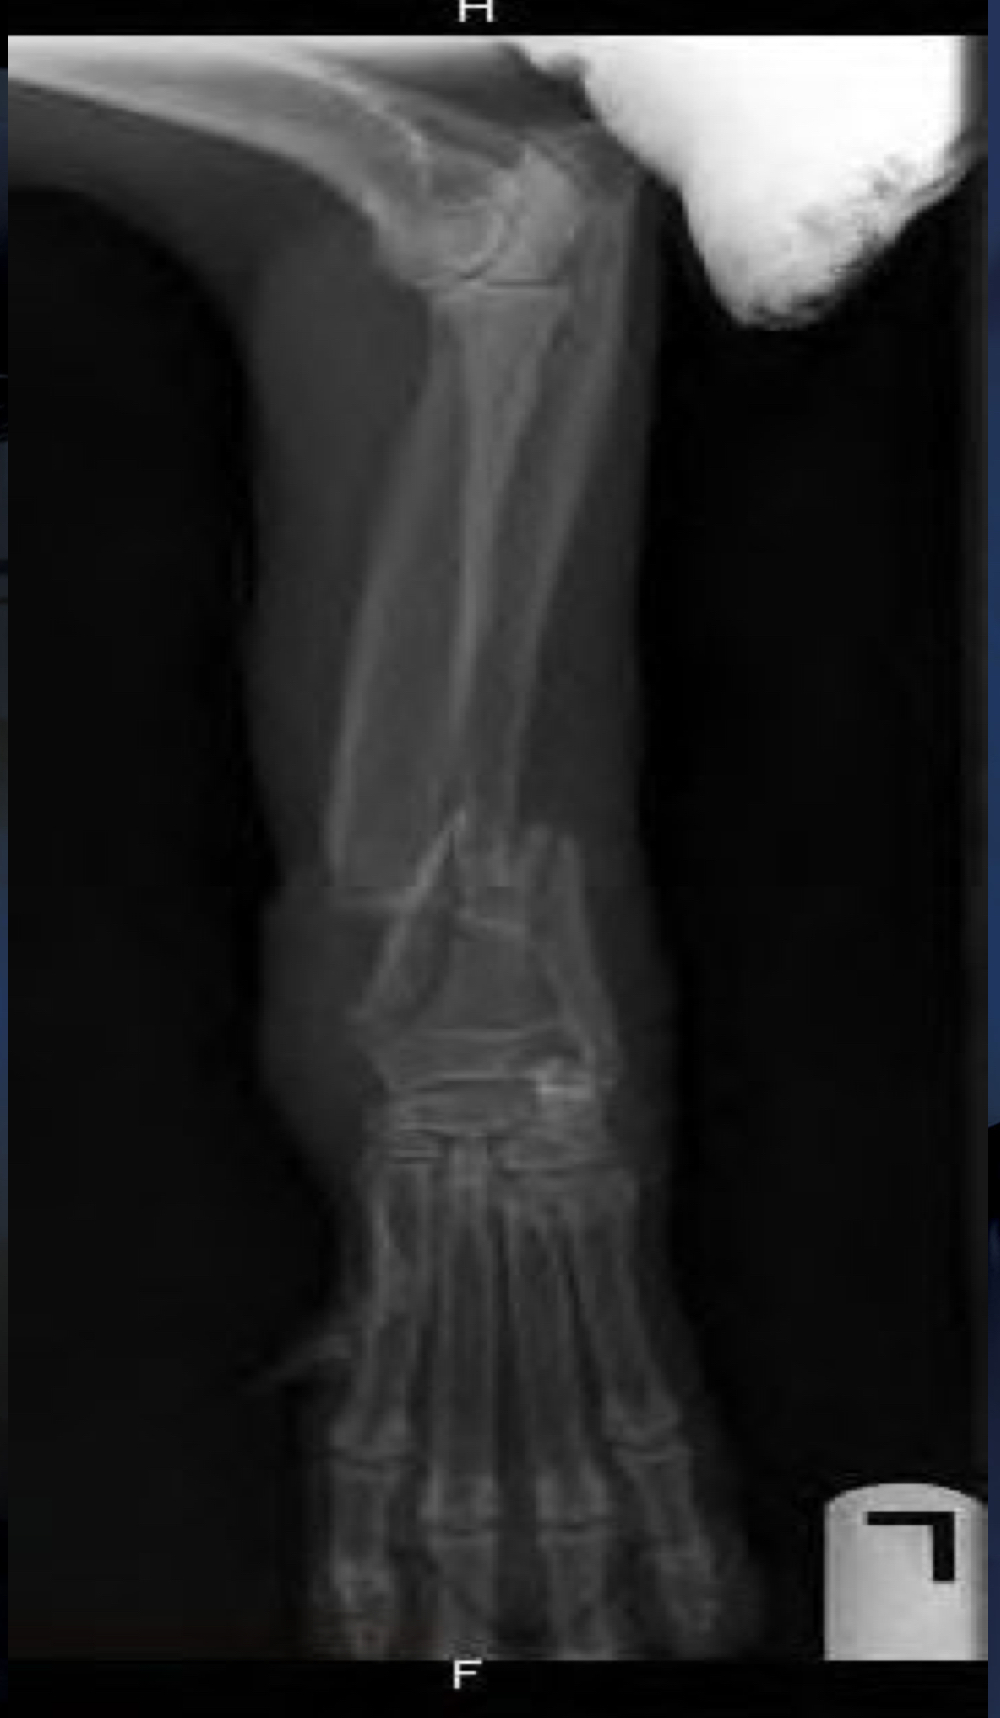

8

Avulsion fracture:

cartilaginous tibial tuberosity